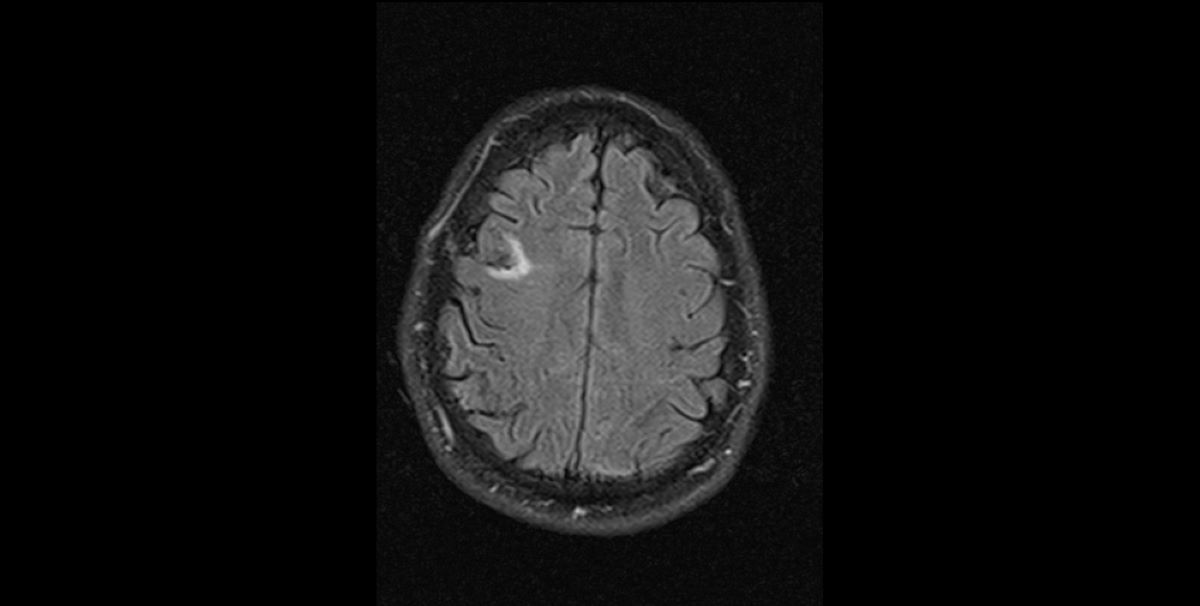

забавнаякартинка из МРТ головного мозга от 13.01.2023 г.